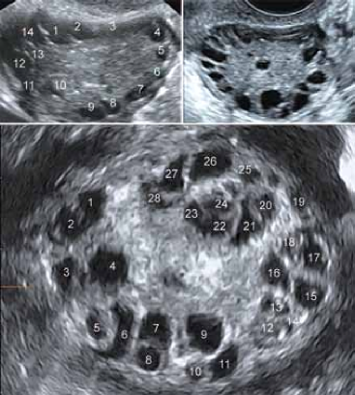

- Ultrasound pelvis- to assess the size and morphology of the ovaries

- Ultrasound pelvis to assess the size of ovaries